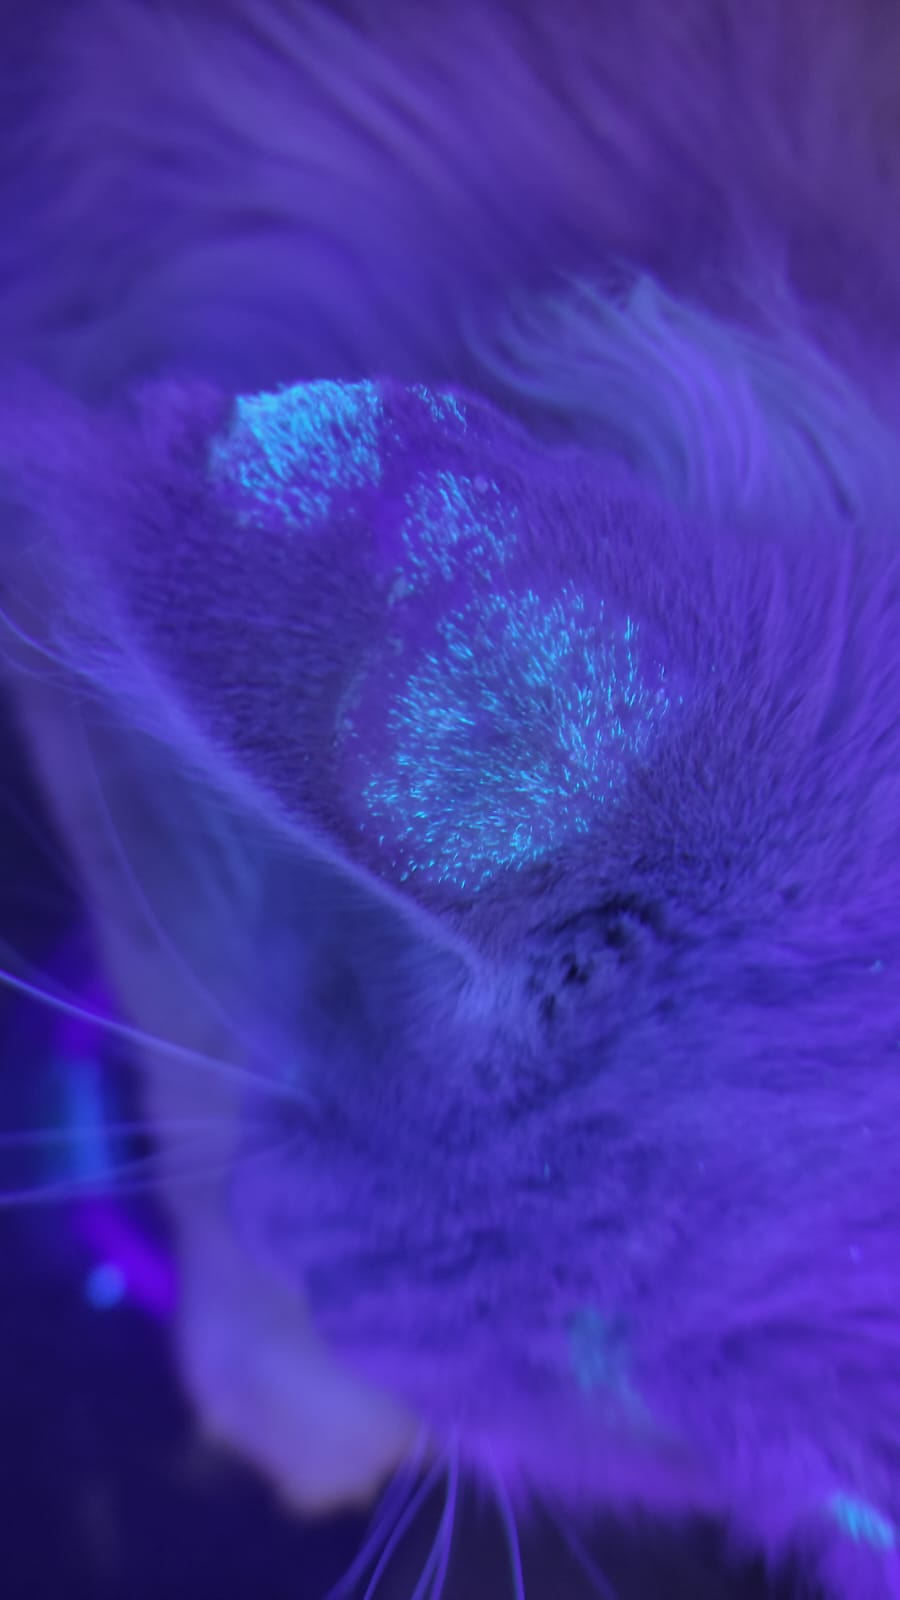

Lâmpada de wood:

Importante para visualização de diversas alterações na pele. Utilizada, sobretudo, para auxiliar no diagnóstico da dermatofitose, uma micose que pode atingir cães, gatos, homem e outras espécies.